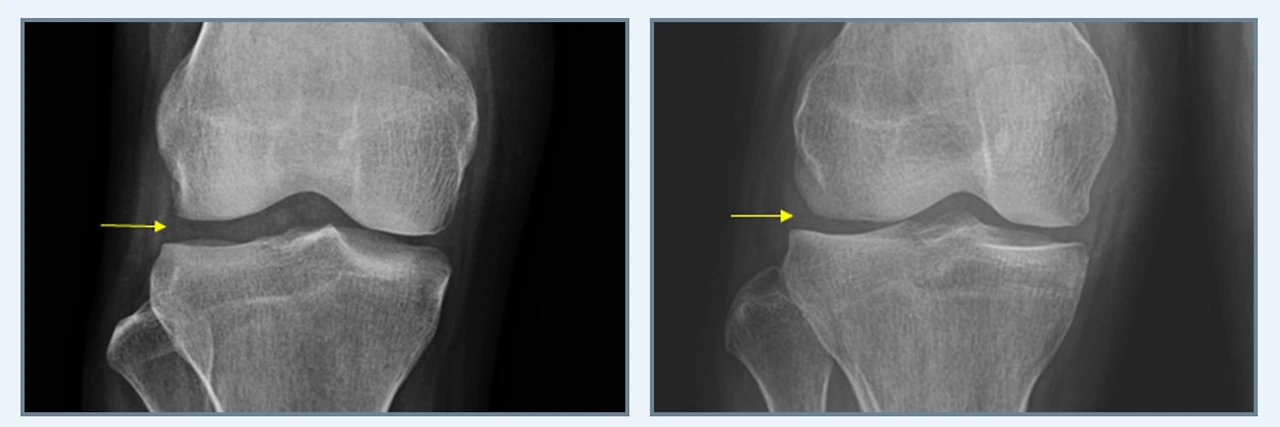

연골판 부분 절제술이란, 파열된 연골판 조직을 제거하고 온전한 연골판 조직을 보존해 기능하도록 하는 수술방식으로, 수평형 파열과 피판형 파열과 같은 파열 형태에 따라 수술이 진행됩니다.

연골판부분절제술.PNG

다음 연골판 봉합술은 연골판의 기능을 보존하기 위해 후각부의 파열을 봉합하는 것으로 체중을 가하거나 심한 운동을 할 경우에 재발할 수 있다는 단점이 있어 면밀한 검사가 필수입니다.